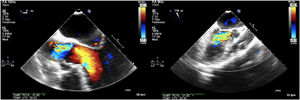

CasoPaciente masculino de 56 años, con antecedente de hipertensión arterial, quien consultó a una institución de tercer nivel de Medellín por cuadro clínico de tres días de evolución consistente en parestesias y hemiparesia del hemicuerpo derecho, asociado a disartria y asimetría facial; negaba síntomas cardiovasculares. Una tomografía de cráneo simple realizada a su ingreso, mostró área hipodensa en región gangliobasal izquierda compatible con lesión isquémica. Se amplió estudio para determinar etiología del infarto cerebral, encontrando VDRL reactivo en 128 dils y FTA-ABS positivo. En ecocardiografía transesofágica se evidenció válvula aórtica trivalva con insuficiencia severa, secundaria a perforación de la valva coronariana derecha, dilatación de la raíz aórtica con engrosamiento intimal difuso y calcificaciones en la unión sinotubular y en la curvatura menor del cayado aórtico (fig. 1). Se practicó arteriografía coronaria en la que se encontró dilatación de la aorta torácica ascendente con formación de aneurisma en el tercio medio del cayado aórtico y oclusión en el ostium de la arteria coronaria derecha. Una angiotomografía de tórax confirmó dilatación aneurismática de la aorta ascendente de 45mm de diámetro (fig. 2). En vista de los hallazgos imagenológicos descritos en presencia de serología reactiva para sífilis, se consideró probable aortitis sifilítica. Se hizo recambio valvular aórtico exitoso, por bioprótesis y bypass aorto-coronario a la descendente posterior (fig. 3). El aneurisma de la aorta ascendente no cumplía criterios de diámetro que obligaran a su corrección. El estudio histológico del material quirúrgico arrojó cambios degenerativos; en la aorta se observó vasa vasorum con infiltrado inflamatorio de células mononucleadas, mientras que la tinción de Warthin-Starry fue negativa.